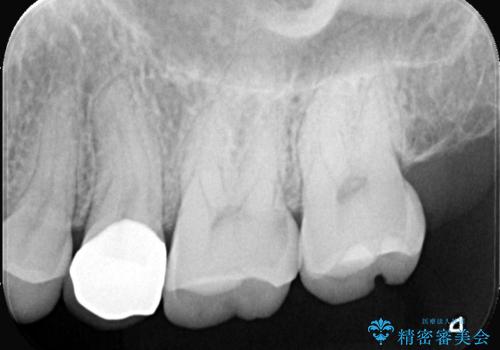

- 銀歯をやり替えたいとのことでした。残っている歯の量や長期的な予後をふまえ、患者様との相談の結果、被せ物での修復となりました。

オールセラミッククラウンを選択されました。

メタルインレーを除去し、その下にあったう蝕を除去したうえで、CRにて築造を行い形成しました。印象時は圧排し、シリコンにて精密に行っています。